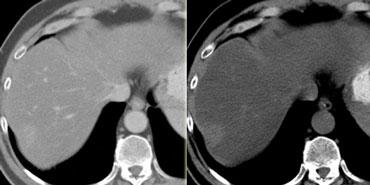

U máu ngấm thuốc nhanh (flash filling) trên thì không tiêm, thì động mạch và thì tĩnh mạch cửa. Lưu ý tỷ trọng tương đương hồ máu.

Các u máu nhỏ có thể biểu hiện ngấm thuốc đồng nhất nhanh chóng (‘flash filling’).

HCC nhỏ và di căn tăng sinh mạch có thể bắt chước u máu nhỏ vì tất cả đều biểu hiện ngấm thuốc đồng nhất trong thì động mạch.

Bằng cách quan sát các thì chụp khác để xem liệu các vùng ngấm thuốc có tương đương hồ máu hay không, thông thường có thể phân biệt được các tổn thương này.